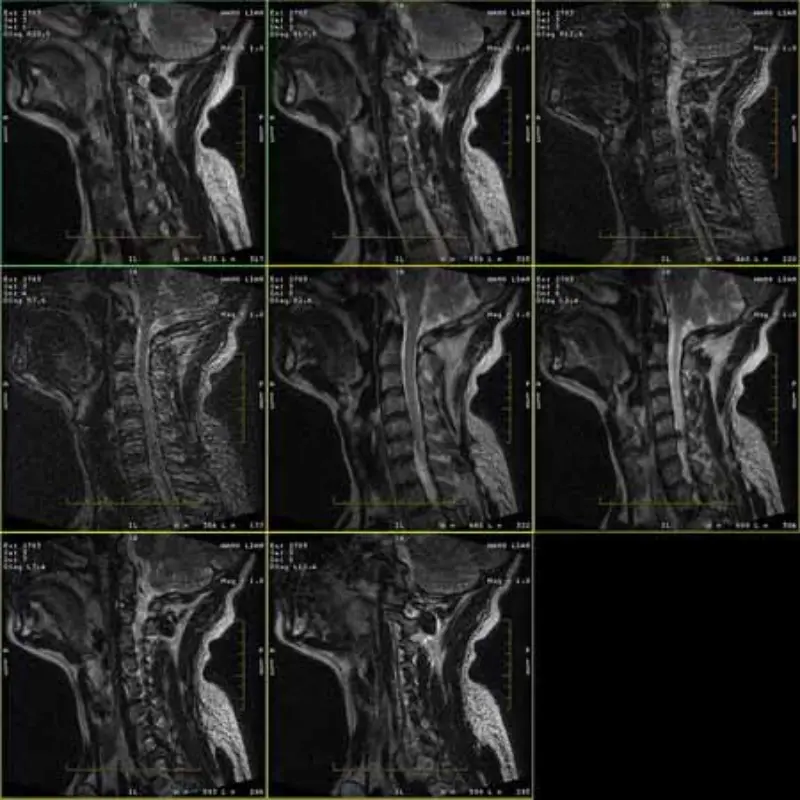

Hình ảnh của giao thức FRFSE và GRE có hiện tượng bóng ma và đôi khi hình ảnh có SNR thấp xuất hiện thành một chuỗi. Nhưng hình ảnh giao thức SE vẫn bình thường.

Xin vui lòng xem hình ảnh đính kèm.